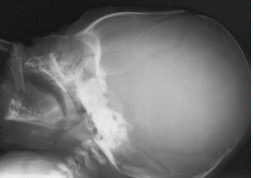

le crâne du foetus est déformable, et peut prendre un aspect surprenant comme le cas ci-dessus (centre). ces déformations se corrigent spontanément en quelques jours à quelques semaines (à droite), n’ont pas de conséquence sur le développement de l’enfant, et ne nécessitent aucune prise en charge particulière.

Les radios ne sont pas indispensables ; si elles sont réalisées, elles montrent la perméabilité de toutes les sutures, ce qui écarte une craniosténose.